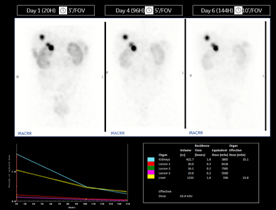

270keVまで対応の検出器で177Luを確実に捉え,Theranosticsをサポート

がんの治療における放射性医薬品内用療法には177Luが用いられることがあるが,その投与量が多いことで従来のSPECT/CT装置では数え落としが発生し,中エネルギー帯であることから半導体であっても208keVのエネルギーを収集することが難しいとされてきた。StarGuideは270keVまでのエネルギーに対応することで,従来のSPECT/CT装置よりも数え落としを圧倒的に少なくし,コリメータを交換せずに177Luにおける113keV, 208keVの双方のエネルギーを収集することが可能になった。画質,定量精度を向上させることで,Theranosticsにおける予後予測,治療における正常臓器への影響をより正確に導き出すサポートを行う。

270keVまで対応の検出器でTheranosticsをサポート